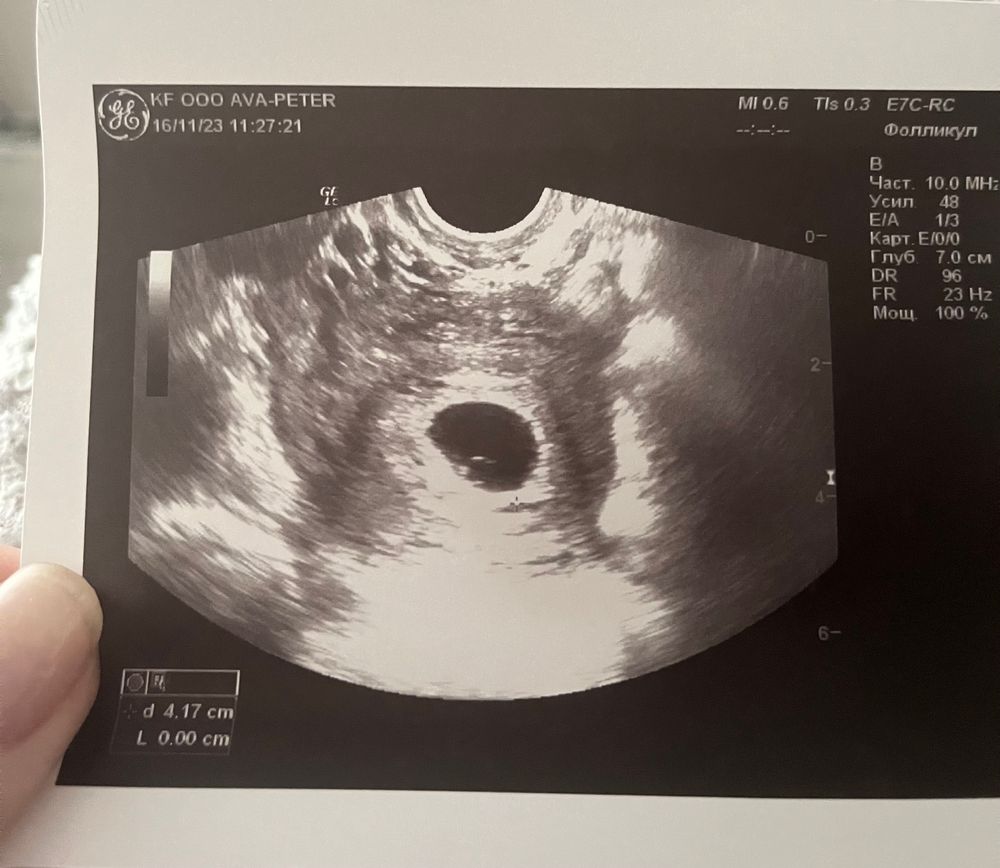

Первое УЗИ на 21дпп☀️

Я БЕРЕМЕННА !Сегодня вручили мне выписной эпикриз после проведенного узи на 21дпп,теперь нужно сделать узи в динамике через 7-10 дней для определения сердцебиения и замеров самого эмбриона.Далее записаться на учет в жк или в платную клинику на выбор.Склоняюсь ко второму варианту🤗Если кто вел беременность в платной клинике в Казани,буду признательна за советы и ваш личный опыт😌А вот и первое фото на память📷ПЯ-15мм,пульсация первичной аорты определяется,желточный мешок определяется(размер почему-то не указан🤷🏻♀️)Теперь снова ждать🤞🏻🌸